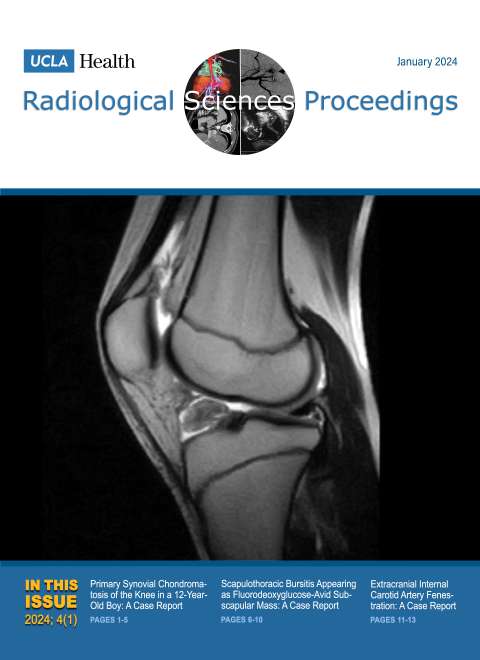

UCLA Radiological Sciences Proceedings

January 2024

Volume 4, Issue 1

- Primary Synovial Chondromatosis of the Knee in a 12-Year-Old Boy: A Case Report

- Scapulothoracic Bursitis Appearing as Fluorodeoxyglucose-Avid Subscapular Mass: A Case Report

- Extracranial Internal Carotid Artery Fenestration: A Case Report